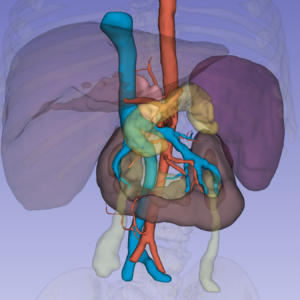

We are pleased to announce that at the 35th Congress of the European Society for Pediatric Urology, held in Vienna from September 3-6, 2025 (https://jointmeeting2025.espu.org), the collaboration between Printmed and the Pediatric Surgery Department of the Vittore Buzzi Children’s Hospital (directed by Professor Gloria Pelizzo) has led to new international recognition, with First Prize in the Video Abstract category for the paper entitled:

ADVANCING NEUROBLASTOMA SURGERY THROUGH VIRTUAL REALITY

(VR) AND INDOCYANINE GREEN (ICG) FLUORESCENCE IMAGING“.

This international recognition demonstrates how, thanks to the ongoing collaboration between Printmed and its clinical counterpart, the use of new surgical technologies such as Virtual Reality can lead to extremely interesting results and clinical applications.